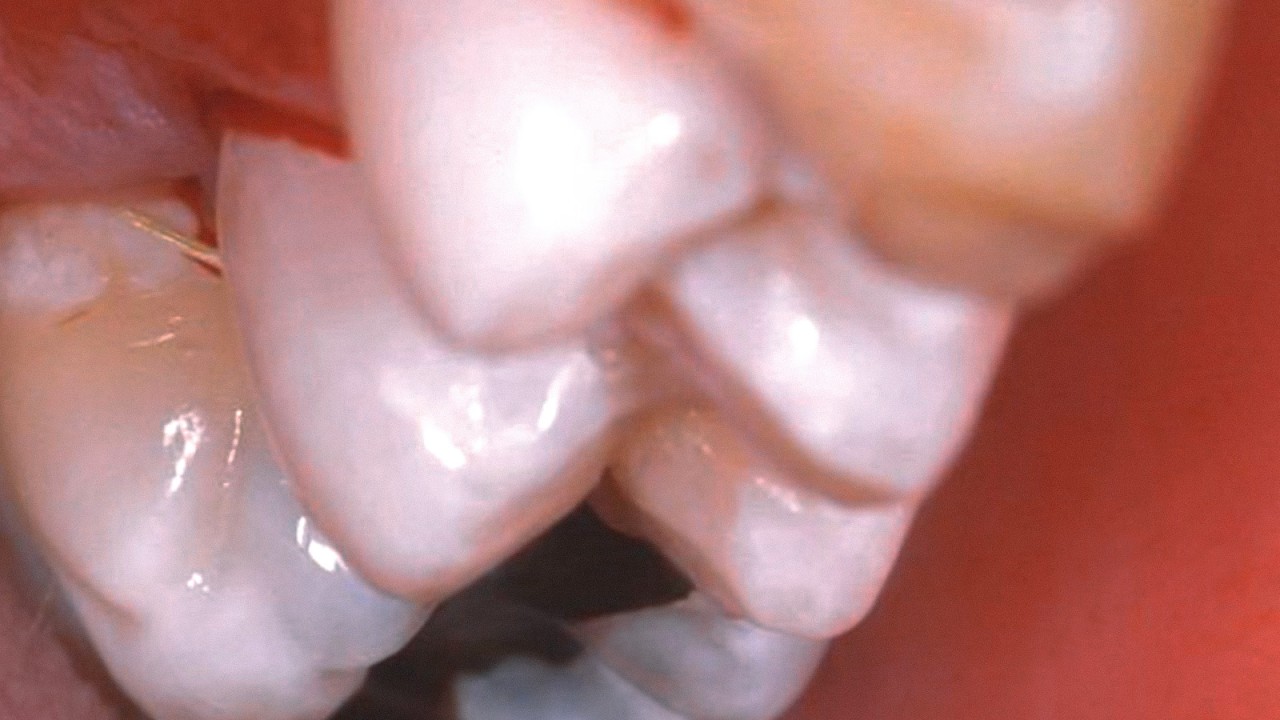

ONE shade cases – great results around the world

Before & After Cases

Life Hacks for successful posterior restorations